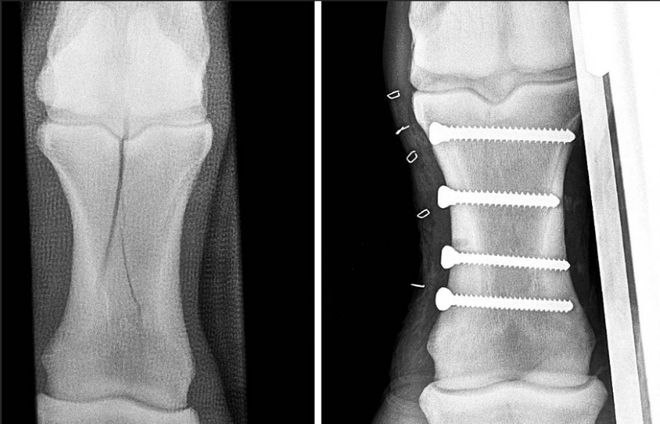

MK体育马一旦骨折真的就“没救了”吗?(图2)

踢伤造成的马第四跖骨骨折。由于该处不直接负重、较稳定,一般休养3个月左右即可。 图源:王炜晗